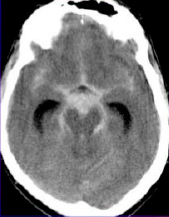

22

¿Qué hematoma es este?

Epidural

23

¿Qué tipo de hematoma es este?

Subaracnoideo (hemorragia)